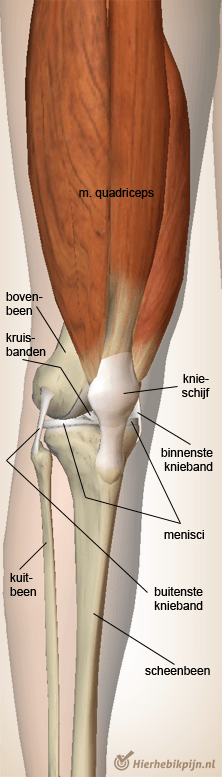

Knie